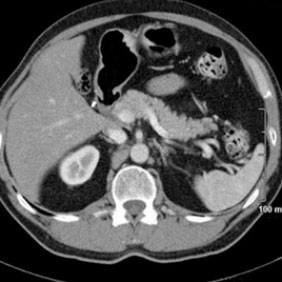

Tomografía computarizada Abdomen

< Volver a "Tomografía Computarizada (TC) con Inteligencia artificial"Se utiliza para el estudio de los diferentes órganos de abdomen y pelvis (hígado, riñones, intestino, próstata, ovarios…).